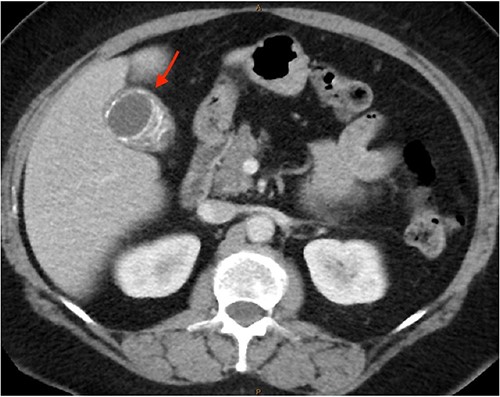

As only part of her gallbladder was imaged on the non-contrast CT lumbar spine, a repeat CT scan of her abdomen and pelvis with portal venous contrast was ordered. This showed semi-annular wall calcification at the gallbladder body suggestive for porcelain gallbladder and several calcified gallstones with largest measuring up to 32 mm (Figs 1–3). No gallbladder soft tissue mass was seen.

Semi-annular wall calcification at the gallbladder body—coronal view.